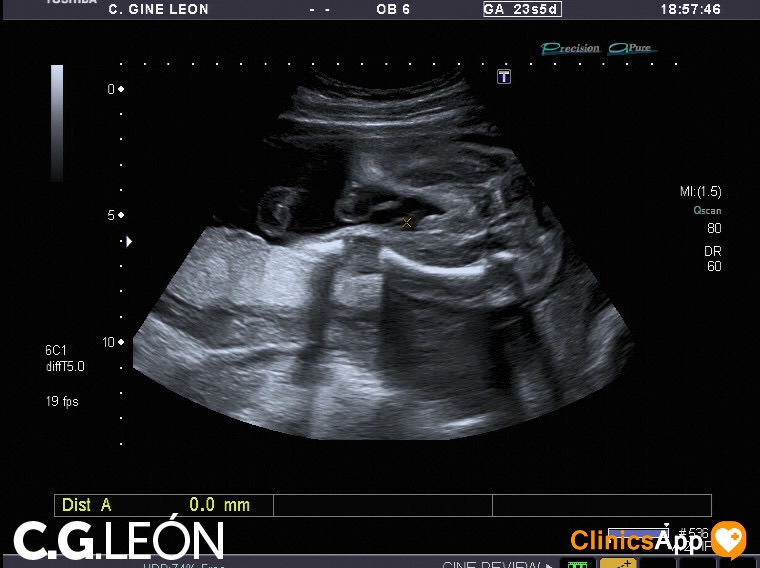

Aquí las fotos de la quinta ecografía, nada que destacar excepto que la ginecóloga estaba de mala leche y no se esmeró demasiado en las fotos. Hay una en la que se ve una mano, en directo se distinguía mejor, claro, porque se vio abierta como en la foto y luego la cerró. Pero por lo general encuentro de difícil interpretación este lote de fotos.